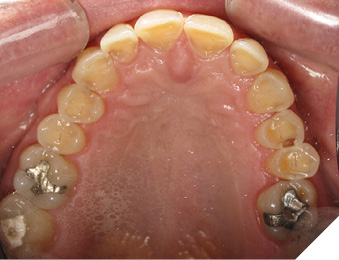

A 65-year-old woman comes to the office with the chief complaint of worn-down teeth, missing teeth, tooth sensitivity, especially on maxillary teeth and TMJ pain. Her past medical history was reviewed and was significant for asthma, insomnia, hypercholesterolemia, hypothyroidism, and anxiety disorder. She denied any sleep disturbances. Her medications included salbutamol, ezetimibe, quetiapine, and levothyroxine. She referred to being allergic to dust and shellfish and sensitive to propofol. She had a right mastectomy in 2014 due to breast cancer. No chemotherapy or radiation was done. Her diet was considered normal, and she denied any consumption of acidic drinks and denied any history of regurgitation. She denied any parafunctional habits during the day. She was using a maxillary transitional partial denture since she had lost some of her teeth due to fracture and caries. No other problems were evidenced. Intraoral exam showed moderate attrition lesions of posterior teeth, porcelain fused to metal crowns on teeth 46 and 47 had the porcelain portion worn down, exposing the metal substructure. Missing teeth included teeth 14,15,16,18,24,28, 36,38,48. Palatal surfaces of maxillary anterior teeth also appeared worn down. An abfraction lesion was found on tooth 23. No carious lesions were found in any of her teeth. Composite restorations on mandibular anterior teeth were chipped or were missing (Figs. 6-11) She also presented with limited mouth opening: 35 mm interincisal distance at maximum opening. There was bilateral pain on palpation of preauricular areas. Her pain was the worst early in the morning which suggested night parafunction. No crepitus, or joint clicking were found.

Fig. 6